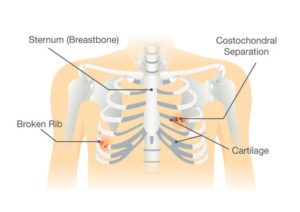

How to diagnose broken ribs. The doctor will first give you an exam to look. If you have a broken rib, symptoms such as bruising, pain and swelling are considered very Press on the injured area.

A broken rib typically causes sharp pain. To diagnose a rib injury, it’s best to see a medical professional who can look at your injuries with professional tools and technology. You may also feel or hear a crack or pop when the.

Sometimes, you may be able to feel a break in your rib by rubbing your finger over the rib. If you have a tender area on your ribs that hurts with every breath, you may have a broken rib. If you heard cracking during the injury or you hear or feel cracking when you move or.

Take slow, deep breaths and cough regularly to expand your lungs, use an incentive spirometer if asked to do so, get up and move around when you’re not sleeping,. When visiting your doctor, they will most likely be able to diagnose your injury simply by pushing on your chest and doing a physical exam. The pain you feel with a broken rib typically occurs or even worsens when you: